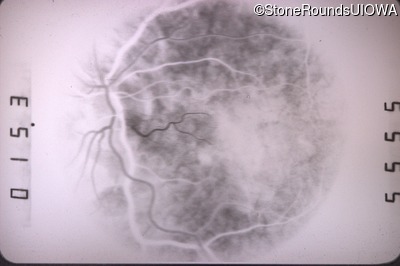

Fluorescein Angiography - Right - 20/50 +2

Exemplar